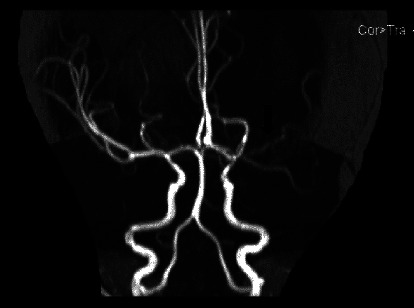

结核性脑膜炎(TBM)是一种严重的结核病,可导致很高的发病率和死亡率,尤其是在延误诊断和治疗的情况下。在本病例报告中,一名 9 个月大的女童因持续呕吐和局灶性抽搐入院。检查发现她右侧偏瘫。脑部影像学检查显示,她的脑膜呈强结节状强化、脑积水、左侧基底节低密度病变、动脉狭窄和血管炎以及陈旧性缺血性损伤。患者最初被诊断为急性缺血性中风,接受了阿司匹林和抗癫痫药物治疗。尽管进行了初步治疗,但患者的病情仍不见好转,于是进行了进一步诊断。结果发现了 TBM 诊断。该病例强调了将 TBM 视为神经系统症状的可能病因的重要性,尤其是在冠状病毒病 2019(COVID-19)大流行期间,严重急性呼吸系统综合征冠状病毒 2(SARS-CoV-2)感染和儿童多系统炎症综合征(MIS-C)的神经系统并发症病例中也可能出现类似症状。

Tuberculous meningitis (TBM) is a serious form of TB disease that can result in high morbidity and mortality, particularly if there are delays in diagnosis and treatment. In this case report, a 9-month-old girl was admitted with persistent vomiting and focal seizures. On examination, she was found to have a right-side hemiparesis. Brain imaging showed intense nodular leptomeningeal enhancement, hydrocephalus, a hypolucent lesion in the left basal ganglia, arterial stenosis and vasculitis, and an old ischemic insult. The patient was initially diagnosed with an acute ischemic stroke and was treated with aspirin and antiepileptic drugs. The patient's condition failed to improve despite initial treatment, leading to further diagnostic procedures. The results uncovered a diagnosis of TBM. The case highlights the importance of considering TBM as a possible cause of neurological symptoms, especially during the coronavirus disease 2019 (COVID-19) pandemic where similar symptoms can be present in cases of neurological complications of severe acute respiratory syndrome coronavirus 2 (SARS-CoV-2) infection and multisystem inflammatory syndrome in children (MIS-C).